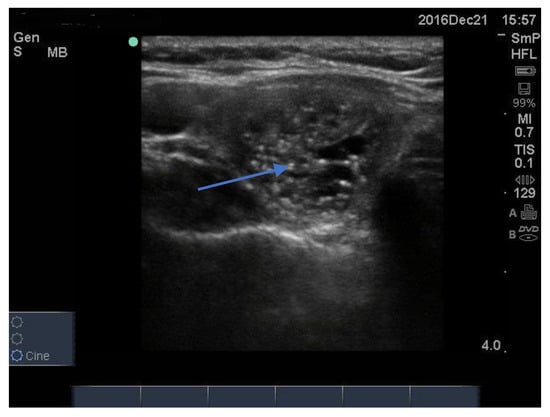

Three examples of papillary thyroid cancer are shown here. Firstly, a large typical papillary cancer with the characteristic microcalcifications is seen in Figure 11.

Figure 11.

Thyroid ultrasound from a patient with confirmed papillary thyroid cancer. The nodule is large (3 cm) and hypoechoic with an indistinct irregular edge and central microcalcifications. The calcifications are softer (less white) than seen above in some benign nodules and larger, around 2–3 mm (arrow). There is no halo. Not seen here, the blood supply was increased in the lesion and there was a feeding vessel on one side of the lesion. Another example of macrocalcifications in papillary thyroid cancer.

Secondly, a smaller but more hypoechoic lesion with obvious and larger soft microcalcifications and an irregular edge is shown in Figure 12. These two nodules are typical for papillary cancer and are reported from FNAB as “suspicious for papillary thyroid cancer”. In both cases this was confirmed at thyroidectomy

Figure 12.

Papillary cancer lesion with large fluffy microcalcifications, an irregular edge and overall hypoechoic texture.